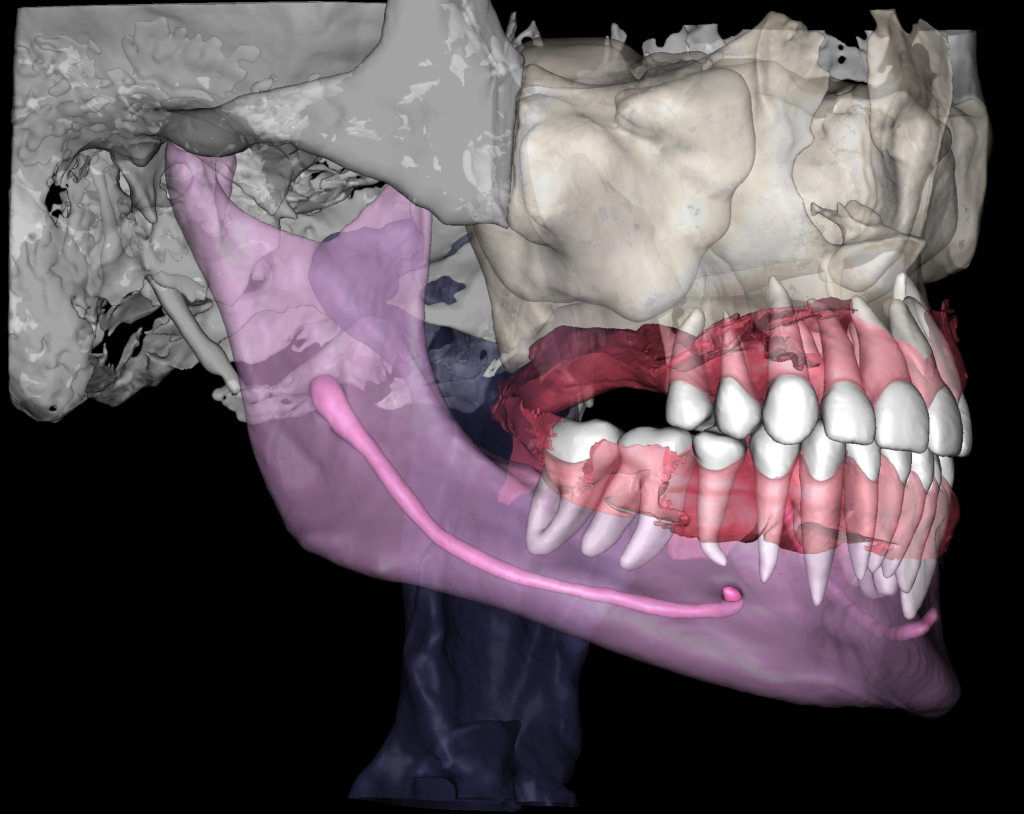

Task: Plan the implant treatment for the replacement of teeth 16 (Universal 3) and 17 (Universal 2), reduce the time required for surgical template fabrication, and improve the accuracy of its fit. Using the “STL” module of Diagnocat, it is possible to create a 3D reconstruction of cone-beam computed tomography (CBCT) and virtual models of templates. To achieve this, intraoral scan data is uploaded into the module, and a suitable CBCT is selected for merging.

Problem:In some clinical cases, it’s difficult to ensure the required accuracy in merging intraoral scanning and CBCT.

Solution: Diagnocat AI provides an advanced solution for identifying CBCT structures using machine learning and artificial intelligence technologies. By combining STL and DICOM data in a unified coordinate system, Diagnocat minimizes errors when creating template models.